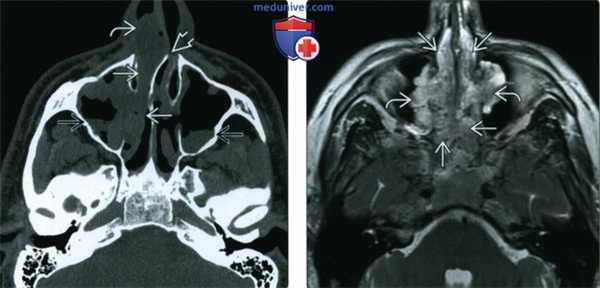

(Слева) При аксиальной «костной» КТ определяются типичные признаки АХП. Пневматизация правой верхнечелюстной пазухи снижена, визуализируется полиповидное мягкотканное образование, пролабирующее в полость носа. Сзади полип пролабирует через хоану в носоглотку.

(Справа) При аксиальной МРТ Т2 FS у ребенка определяется гиперинтенсивный АХП слева. Видны антральный и носоглоточный ва компоненты. АХП гиперинтенсивнен по сравнению с нижней носовой раковиной.